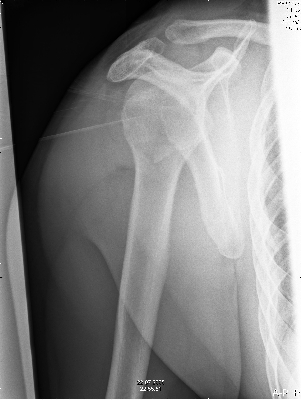

Nadat deze was terug gezet zag het er weer goed uit. |

Maar op 9 augustus bleek dan niet zo te zijn en moest er de volgende dag geopereerd worden. |

| na de operatie was alles weer vast gezet. |